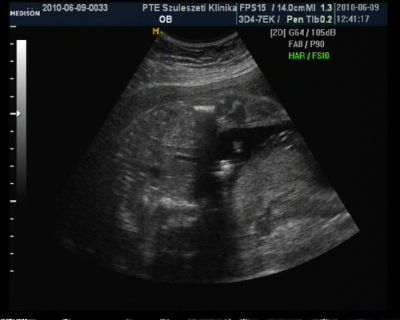

Az első két képen a drága szerszáma látszik!

Úgy feküdt a drága mint aki hátra bukfencet csinál doki is csak nézett.. de így a kukki lelógott :)